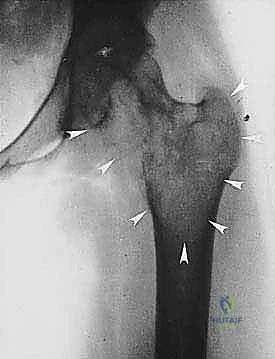

* الساركوما العظمية (Osteosarcoma): الأكثر شيوعاً، تظهر عادة حول الركبة (أسفل الفخذ أو أعلى القصبة).

| حدود الورم في الأشعة | واضحة، محددة بدقة (Sclerotic margin) | غير واضحة، متآكلة (Moth-eaten appearance) |

| اختراق قشرة العظم | نادر جداً | شائع جداً، يمتد للأنسجة الرخوة المحيطة |

2. الموقع (Site - T): هل الورم داخل الحيز العظمي (Intracompartmental - T1) أم اخترق القشرة وخرج للحيز الخارجي (Extracompartmental - T2)؟